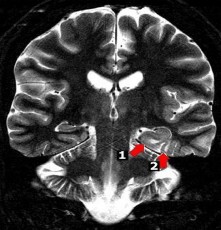

Hình 1.7. Xơ hóa hồi hải mã trái kèm teo thùy thái dương bên trái

Nguồn trích dẫn: Hiba AH, Lawrence JH. Uptodate. 2018; Topic 14040 [29].